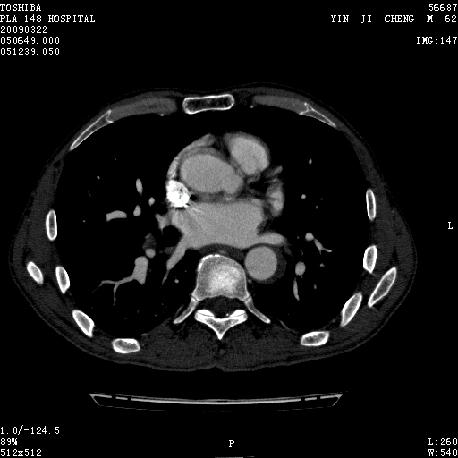

男 62 夜间突然腹痛并向背部放射 ,急诊疑胰腺炎 ,胰淀粉酶正常 ,ct示胰腺未见明显异常,发现降主动脉密度欠均,做主动脉造影示胸腹主动脉半月形低密度充盈缺损,内膜钙化并内移,累及腹腔干致根部明显狭窄,未见明显破裂口。 本人为是不典型夹层,其他人有说是动脉硬化或动脉炎的。请大家发表一下看法。

主动脉附壁血栓?主动脉夹层?

我觉得这个不像主动脉夹层,应该是血栓多点,如果可以重建个mpr也许对诊断更有帮助。